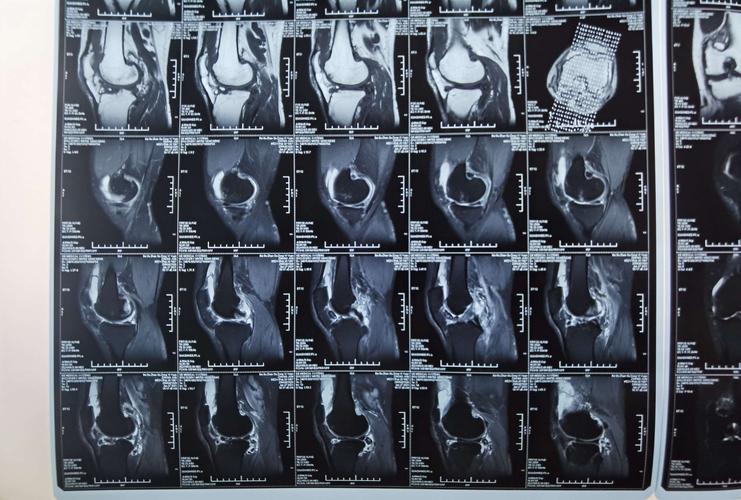

正常膝关节核磁共振图

正常膝关节核磁共振图,前交叉韧带损伤图像

术前核磁共振

谁会看膝关节核磁共振图啊急急

本来考虑半月板桶柄样损伤,但是核磁共振结果有点儿出乎意料,除了关节